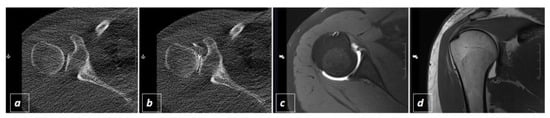

Evaluation of CT-Guided Ultra-Low-Dose Protocol for Injection Guidance in Preparation of MR-Arthrography of the Shoulder and Hip Joints in Comparison to Conventional and Low-Dose Protocols

2.2. CT-Guided Joint Injections

2.3. The Three Different Examination Protocols